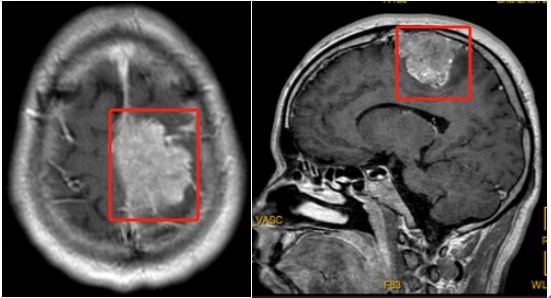

磁共振下的巨大肿瘤

经过详细检查,发现他的颅内矢状窦旁有一个巨大的脑膜瘤,尺寸竟达到了5.6厘米。这个肿瘤对神经系统造成了压迫,是导致他出现肢体无力和感觉障碍的根源。